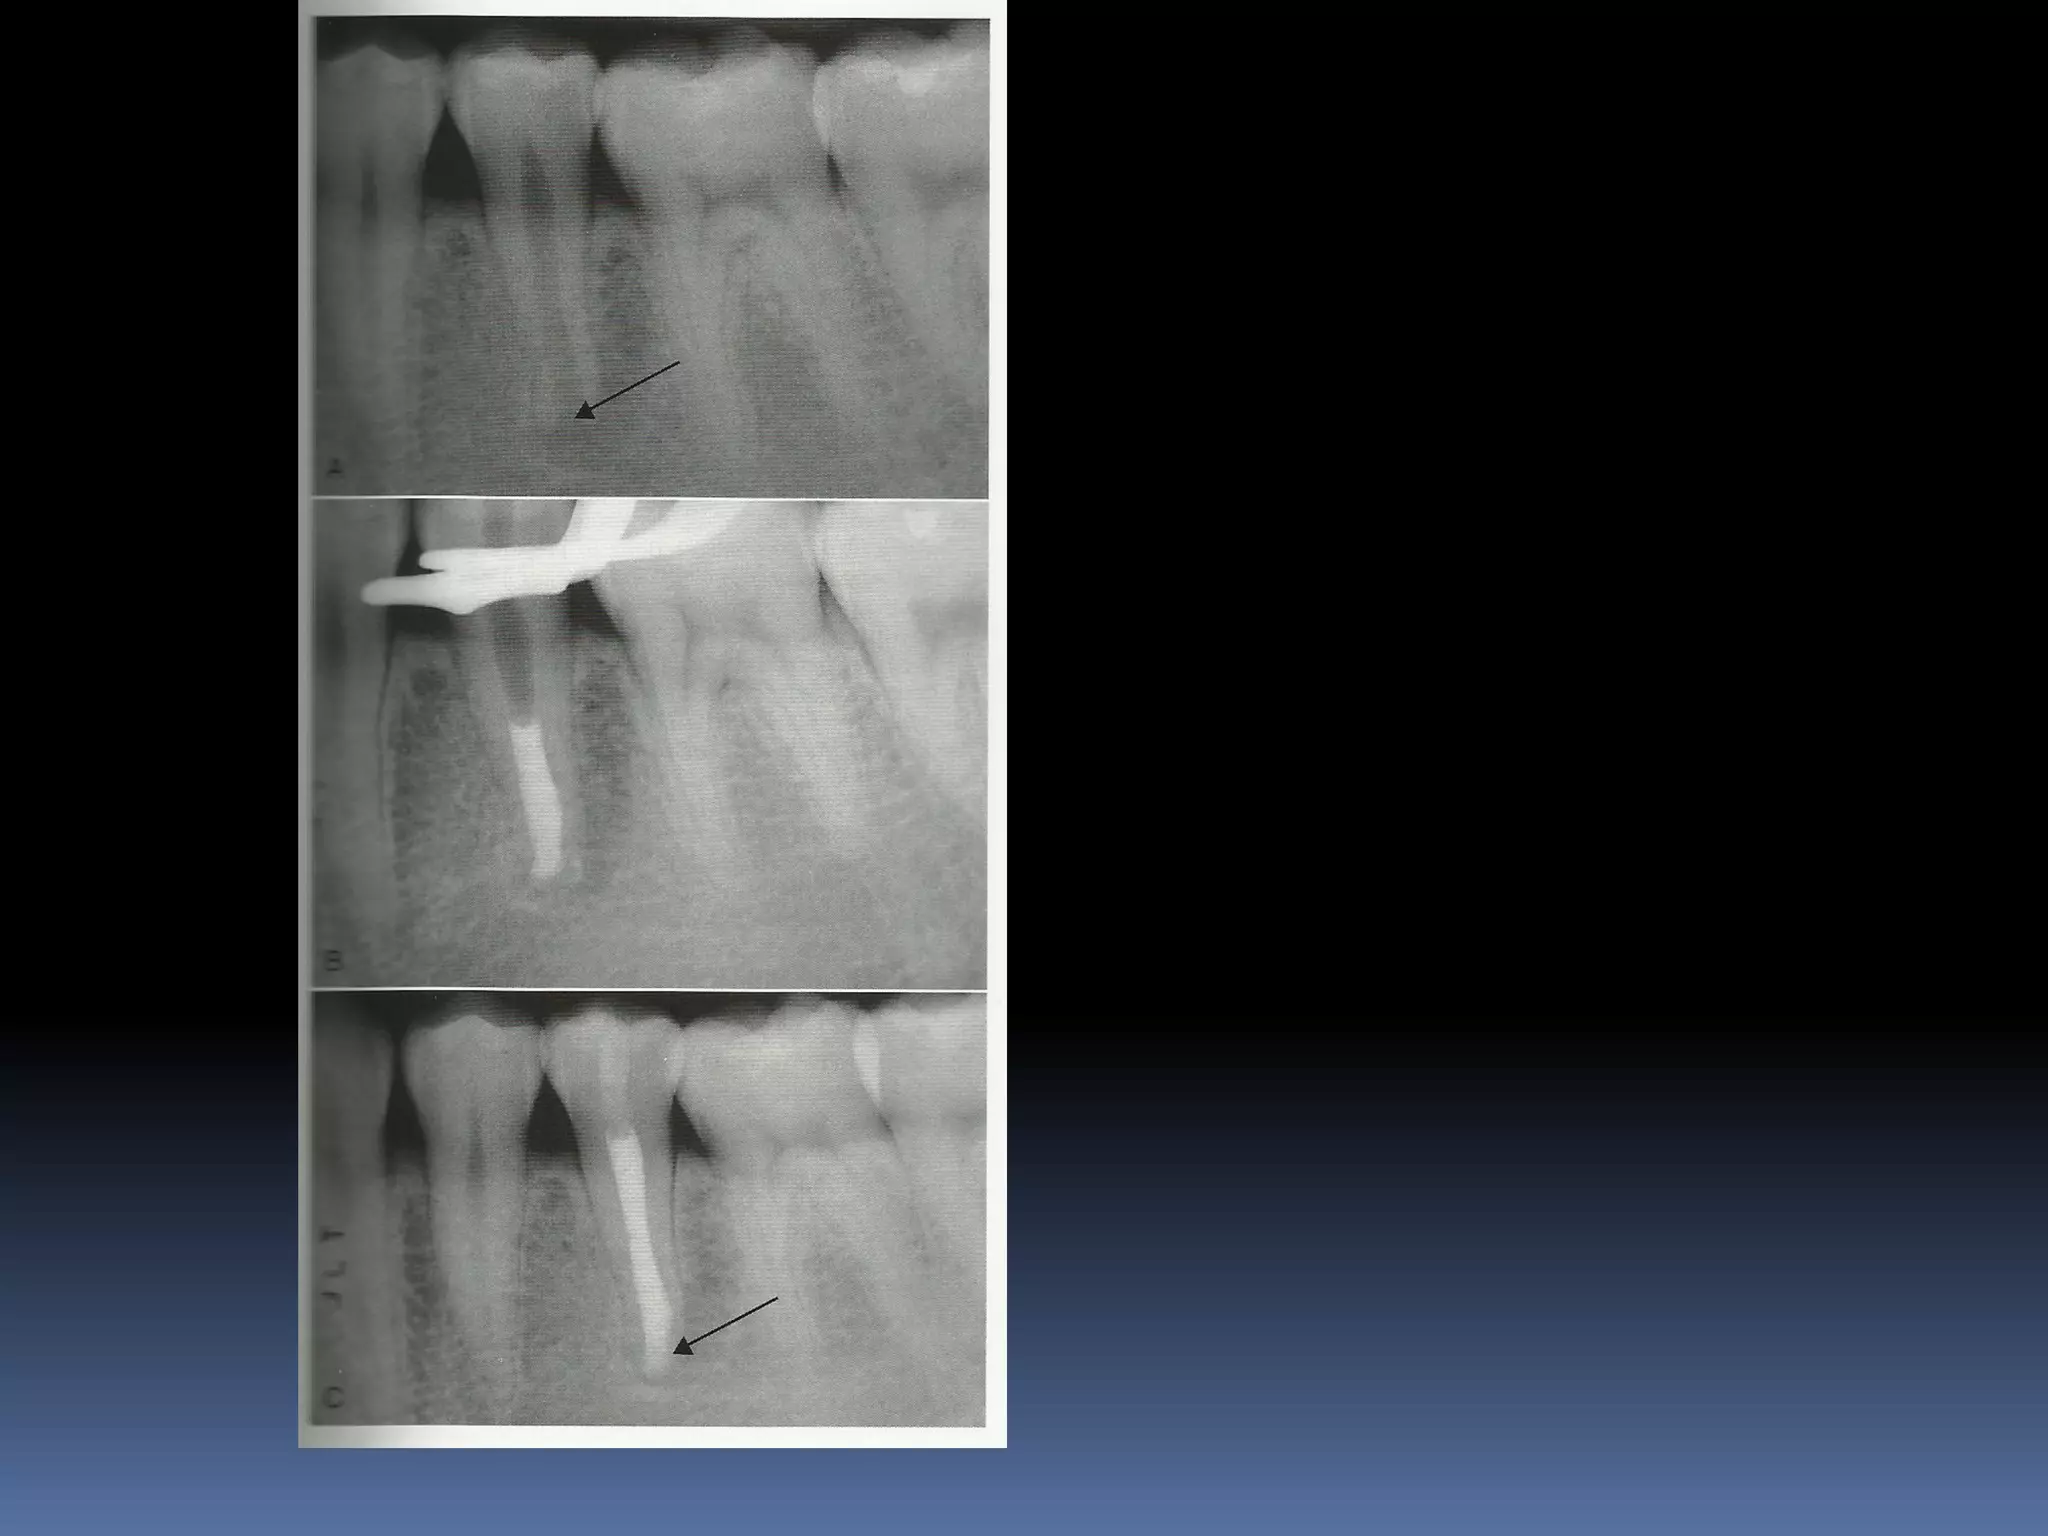

OPEN APEX  Anopen apex is the developing root of an immature tooth until apical closure occurs .  Apical closure occurs 2-3 yrs after tooth eruption  Any injury to the pulp at this stage will stop the closure of the apex  Such a tooth will have short , thin walls at the apical portion of the root

 Open apexcan also be caused by extensive resorption of a previously mature apex after orthodontic treatment or severe periapical inflammation

Diagnosis and assessment: History  Subjective symptoms  Diagnostic tests  Radio graphs A radiolucent area usually surrounds the apex of an immature root with a healthy pulp

APEXOGENESIS A Vital Pulp Therapyprocedure performed to encourage continued physiologic development and formation of the root end. Since the main objective is to maintain the vitality of the radicular pulp the pulp must be vital and capable of repair

APEXIFICATION Induction of acalcific barrier or creation of an artificial barrier across an open apex Technique: Local anesthesia and Rubber Dam isolation Access cavity preparation and extirpation of the pulp Working length is established slightly short of the apex [to prevent injury to apical tissues] Instrumentation and copius irrigation Drying the canal and introducing MTA into the canal

 Packing MTAusing endodontic pluggers or special system like MAP SYSTEM [Micro Apical placement]  MTA acts as an artificial barrier against which Gutta percha can be condensed.  Calcium hydroxide produces a biologic barrier but takes longer time.